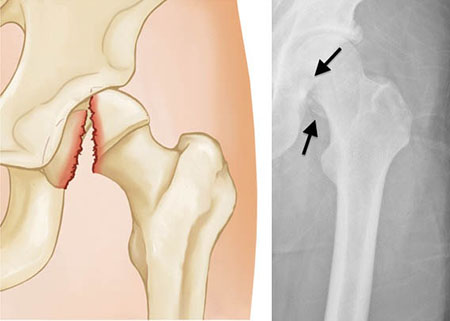

Femoral Neck Fracture

This type of fracture is also sometimes called a subcapital or intracapsular fracture.

If a femoral neck fracture is not displaced (meaning the pieces of bone are properly aligned), the most common treatment is in-situ fixation.

In this procedure, surgical pins/screws or a plate and screw device are passed across the fracture site to hold the ball of the femur in place while the fracture heals. This procedure prevents the femoral head from dislodging or slipping off of the femoral neck, a situation that would require partial or total hip replacement. Both options provide stability to allow for immediate mobilization (getting out of bed and moving around)

Nondisplaced femoral neck fracture

Displaced fractures of the femoral neck present a more difficult problem than nondisplaced fractures. The blood supply to the head of the femur comes through a structure called the posterior capsule. The posterior capsule is often injured with a displaced femoral neck fracture, so the fracture has less chance of healing.

Displaced femoral neck fracture